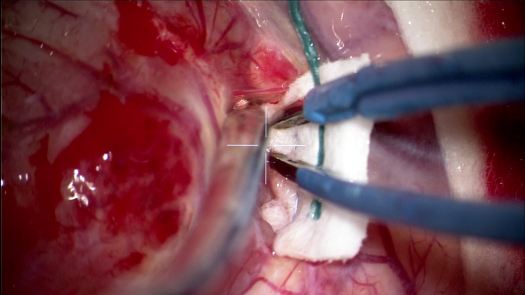

Resezione microchirurgica di tumore cerebrale (glioma alto grado cortico-sottocorticale) frontale dx